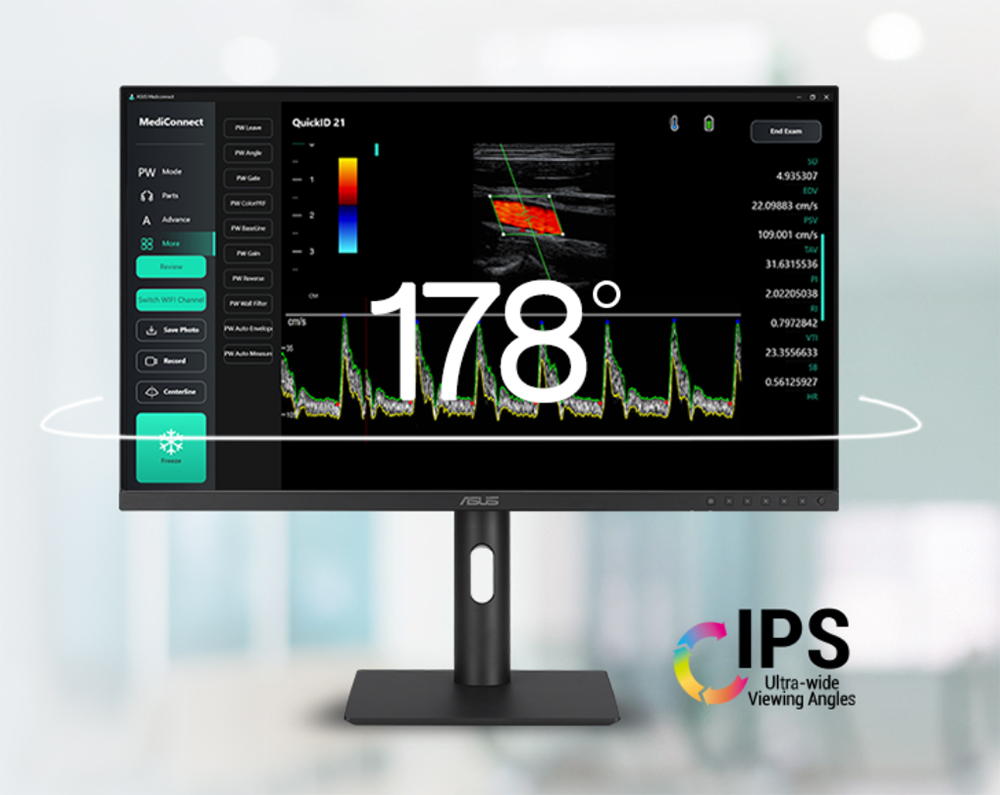

178° geniş izleme açısı

asus ha2441a ıps panel, hem yatay hem de dikey eksenlerde 178° izleme açısı sunar. bu sayede mükemmel kontrast üretebilir ve her yönden net ve hassas tıbbi görseller elde edebilirsiniz.